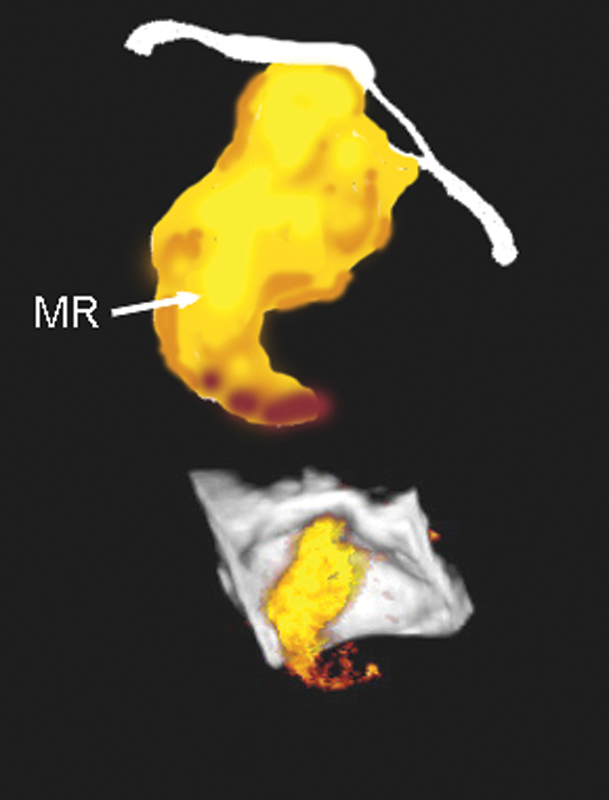

فحوصات تشخيصية لبعض امراض القلب والشرايين التاجية